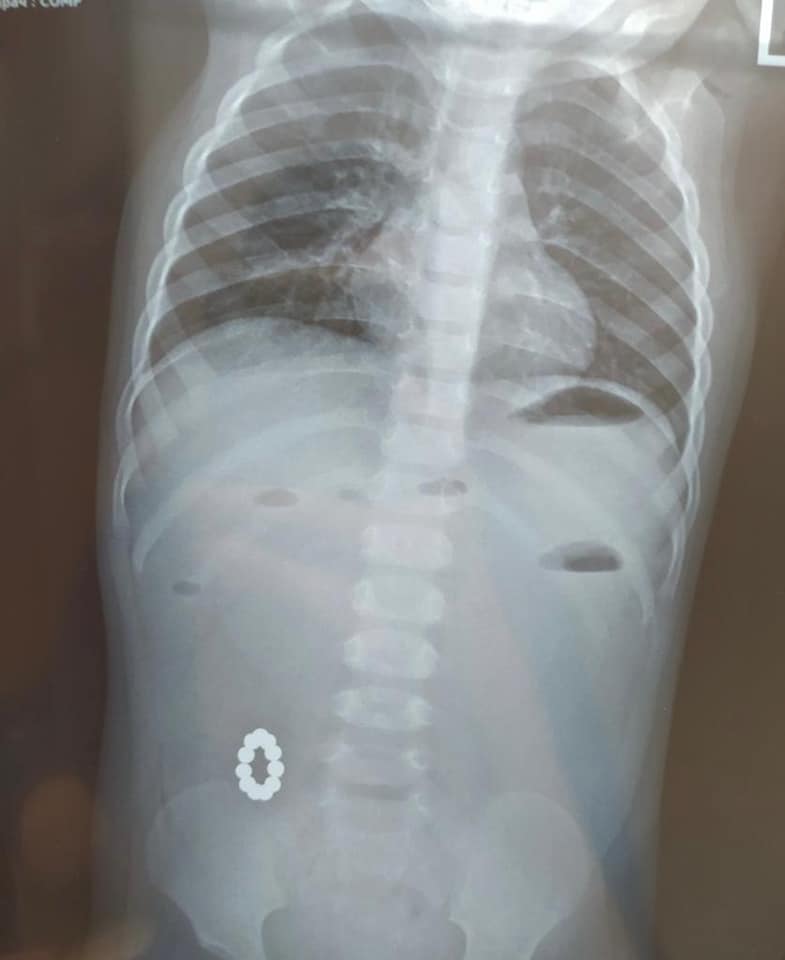

До медустанови маленький пацієнт потрапив з підозрою на харчове отруєння, але при діагностиці виявили, що в кишківнику знаходяться магніти типу “Неокуб”, які з’єдналися між собою і склалися в кільце.

“На цей раз вони привели до тяжкої хірургічної патології – непрохідності кишківника! Ми вже не одноразово звертали увагу батьків на ці небезпечні іграшки особливо для малечі!” – наголошується в публікації.

Також в лікарні опублікували фото рентгена і самої іграшки, яку витягли після операції.